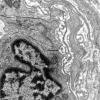

PERIPHERAL NEUROPATHY

11 VASCULITIS - VASCULOPATHY

2 Vasculopathy (7)